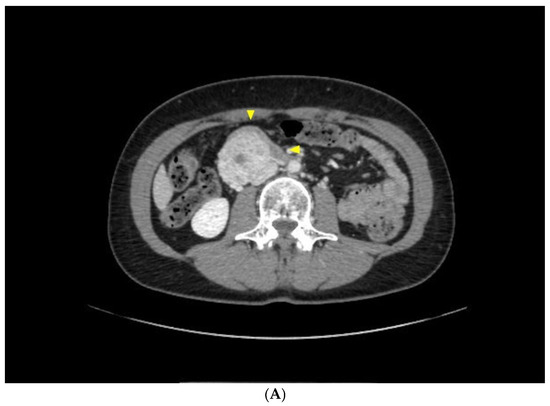

2.1. Case Report 1

2.2. Case Report 2